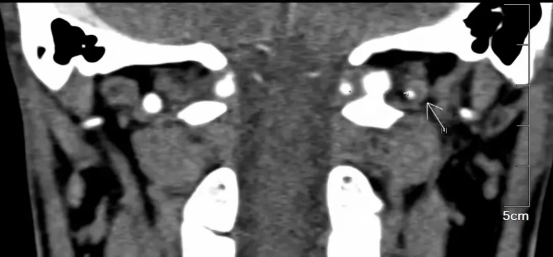

图为患者的头颈联合CTA,考虑左椎动脉V3段夹层伴附壁血栓形成

为进一步明确夹层的位置、长度以及血流情况并进一步治疗,脑五科团队为患者进行脑血管造影检查明确为椎动脉夹层,血流良好,不需要血管内治疗。经积极抗凝等治疗,宋先生头晕及双下肢无力等症状基本消失。